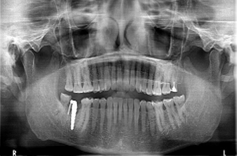

Figure 2: 2 zirconia implants in the 4th quadrant posteriorly.

Figure 3: OPG of zirconia implant in one of our patients